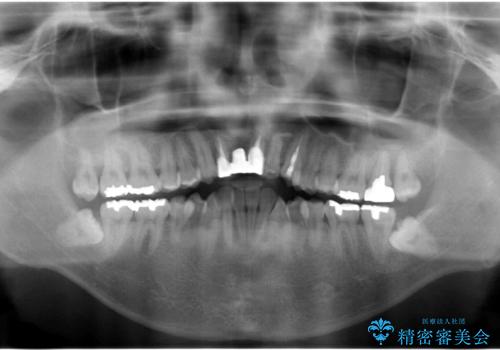

- 前歯のブリッジのやりかえおよび銀の詰め物をセラミックにしたいと来院。

過去に事故で前歯を折って、ブリッジにしたとのことでしたが、支台となる歯が持たない状況で、ブリッジを延長せざるを得ない状況でした。

長いブリッジへ設計変更になるため、下の前歯のがたつきが気になるのであれば、先に矯正治療をしてから最終的なブリッジを入れることをご提案し、全て行なっていくことになりました。

上の前歯の本数が少ないことから、小臼歯を4本抜歯するのではなく下の前歯を1本だけ減らして並べました。

左上1番は再根管治療を行いましたが途中で破折が確認されたため、抜歯しています。

また、大臼歯の銀歯もセラミックに全てやりかえています。

左上7番は歯周病によりやむなく抜歯となり、インプラントをおすすめしましたが、希望されませんでした。